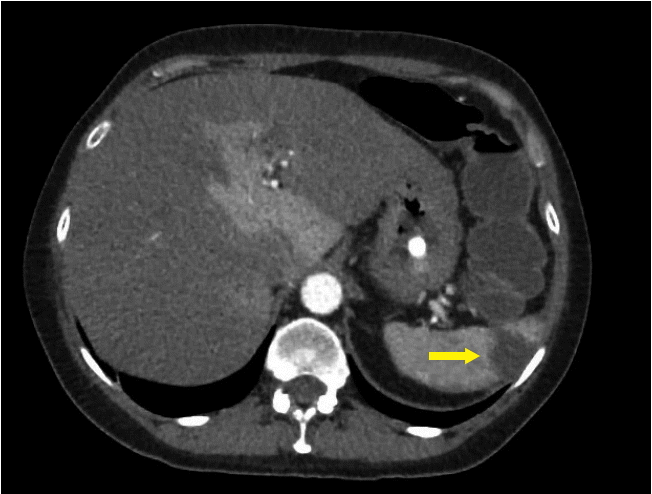

On day 2 of her admission, she developed worsening abdominal pain and rectal bleeding with no relief from opioid analgesia. A thrombophilia and vasculitis screen did not identify a cause and she was treated empirically with therapeutic enoxaparin. By day 4, she had on-going pain refractory to opioid analgesia so a CT angiogram was performed which revealed a nearly occlusive thrombus within the superior mesenteric artery and diffusely thickened loops of small bowel suggestive of ischemia, plus focal areas of nonenhancement within the liver suggestive of hepatic infarction (Fig. 4). There were no features to suggest aortitis.